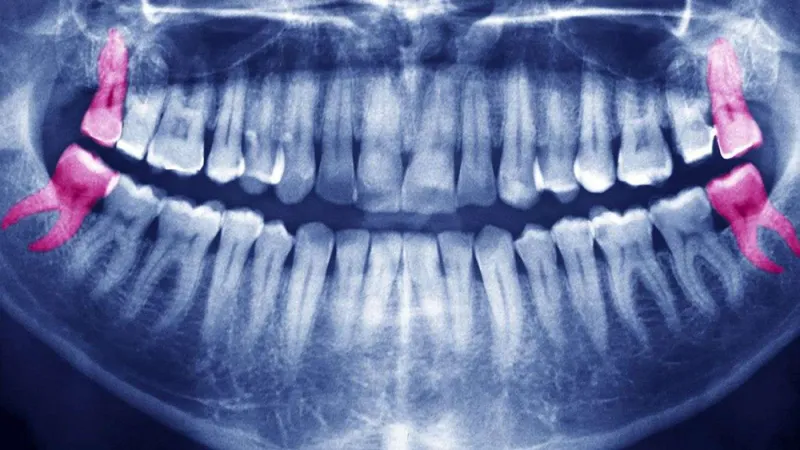

لا تملك أضراس العقل

٢٠٪ من البشر لا يملكون ضرس العقل وهي حالة نادرة بإعتدال. عادة الإنسان «الطبيعي» يملك ٤ أضراس عقل واحد في كل ركن من أركان الفم. وظيفتها عند أسلافنا كانت مساعدتهم على تناول الطعام الذي كان قاسياً وغير مطبوخ أما حالياً فعملياً لا وظيفة لها ولكن تطورنا كبشر لم يصل الى مرحلة تجعلها تختفي كلياً. في الواقع هناك ما هو مثير للإهتمام فعلاً لأن عدم تكون ضرس العقل يختلف بحسب المناطق، فعند السكان الأصليين في تاسمانيا في أستراليا جميعهم لا يتكون لهم ضرس عقل على الإطلاق. أما سكان المكسيك الأصليين فـ ١٠٠٪ منهم يتكون لهم ضرس عقل. الإختلاف هذا يرتبط بشكل أساسي بالجين بي أي أكس تسعة وعلى الارجح بجينات أخرى.